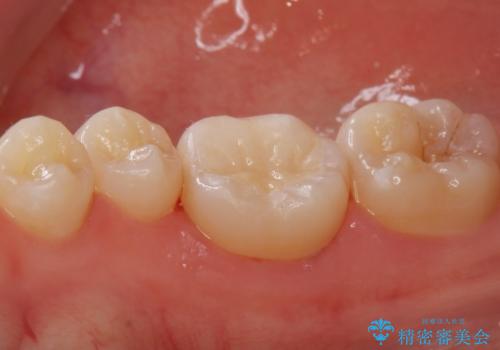

セラミックインレー治療

- 口を開けたとき銀歯が見えるのが嫌で白くしたいとの事で来院。

銀歯を除去してセラミックインレー(e-maxインレー)での治療となりました。

- e-maxインレー 7.7万円 費用は治療当時の料金となります

白い詰め物(e-maxインレー)にしたことにより、口を開けたとき目立たなくなりました。